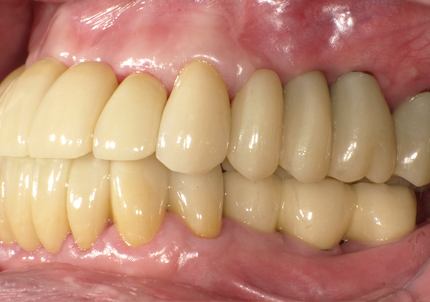

22.最終補綴物完成・装着口腔内写真(2021年1月)

24.口腔内写真

【 2018年 術前 】

【 2025年5月 現在 】